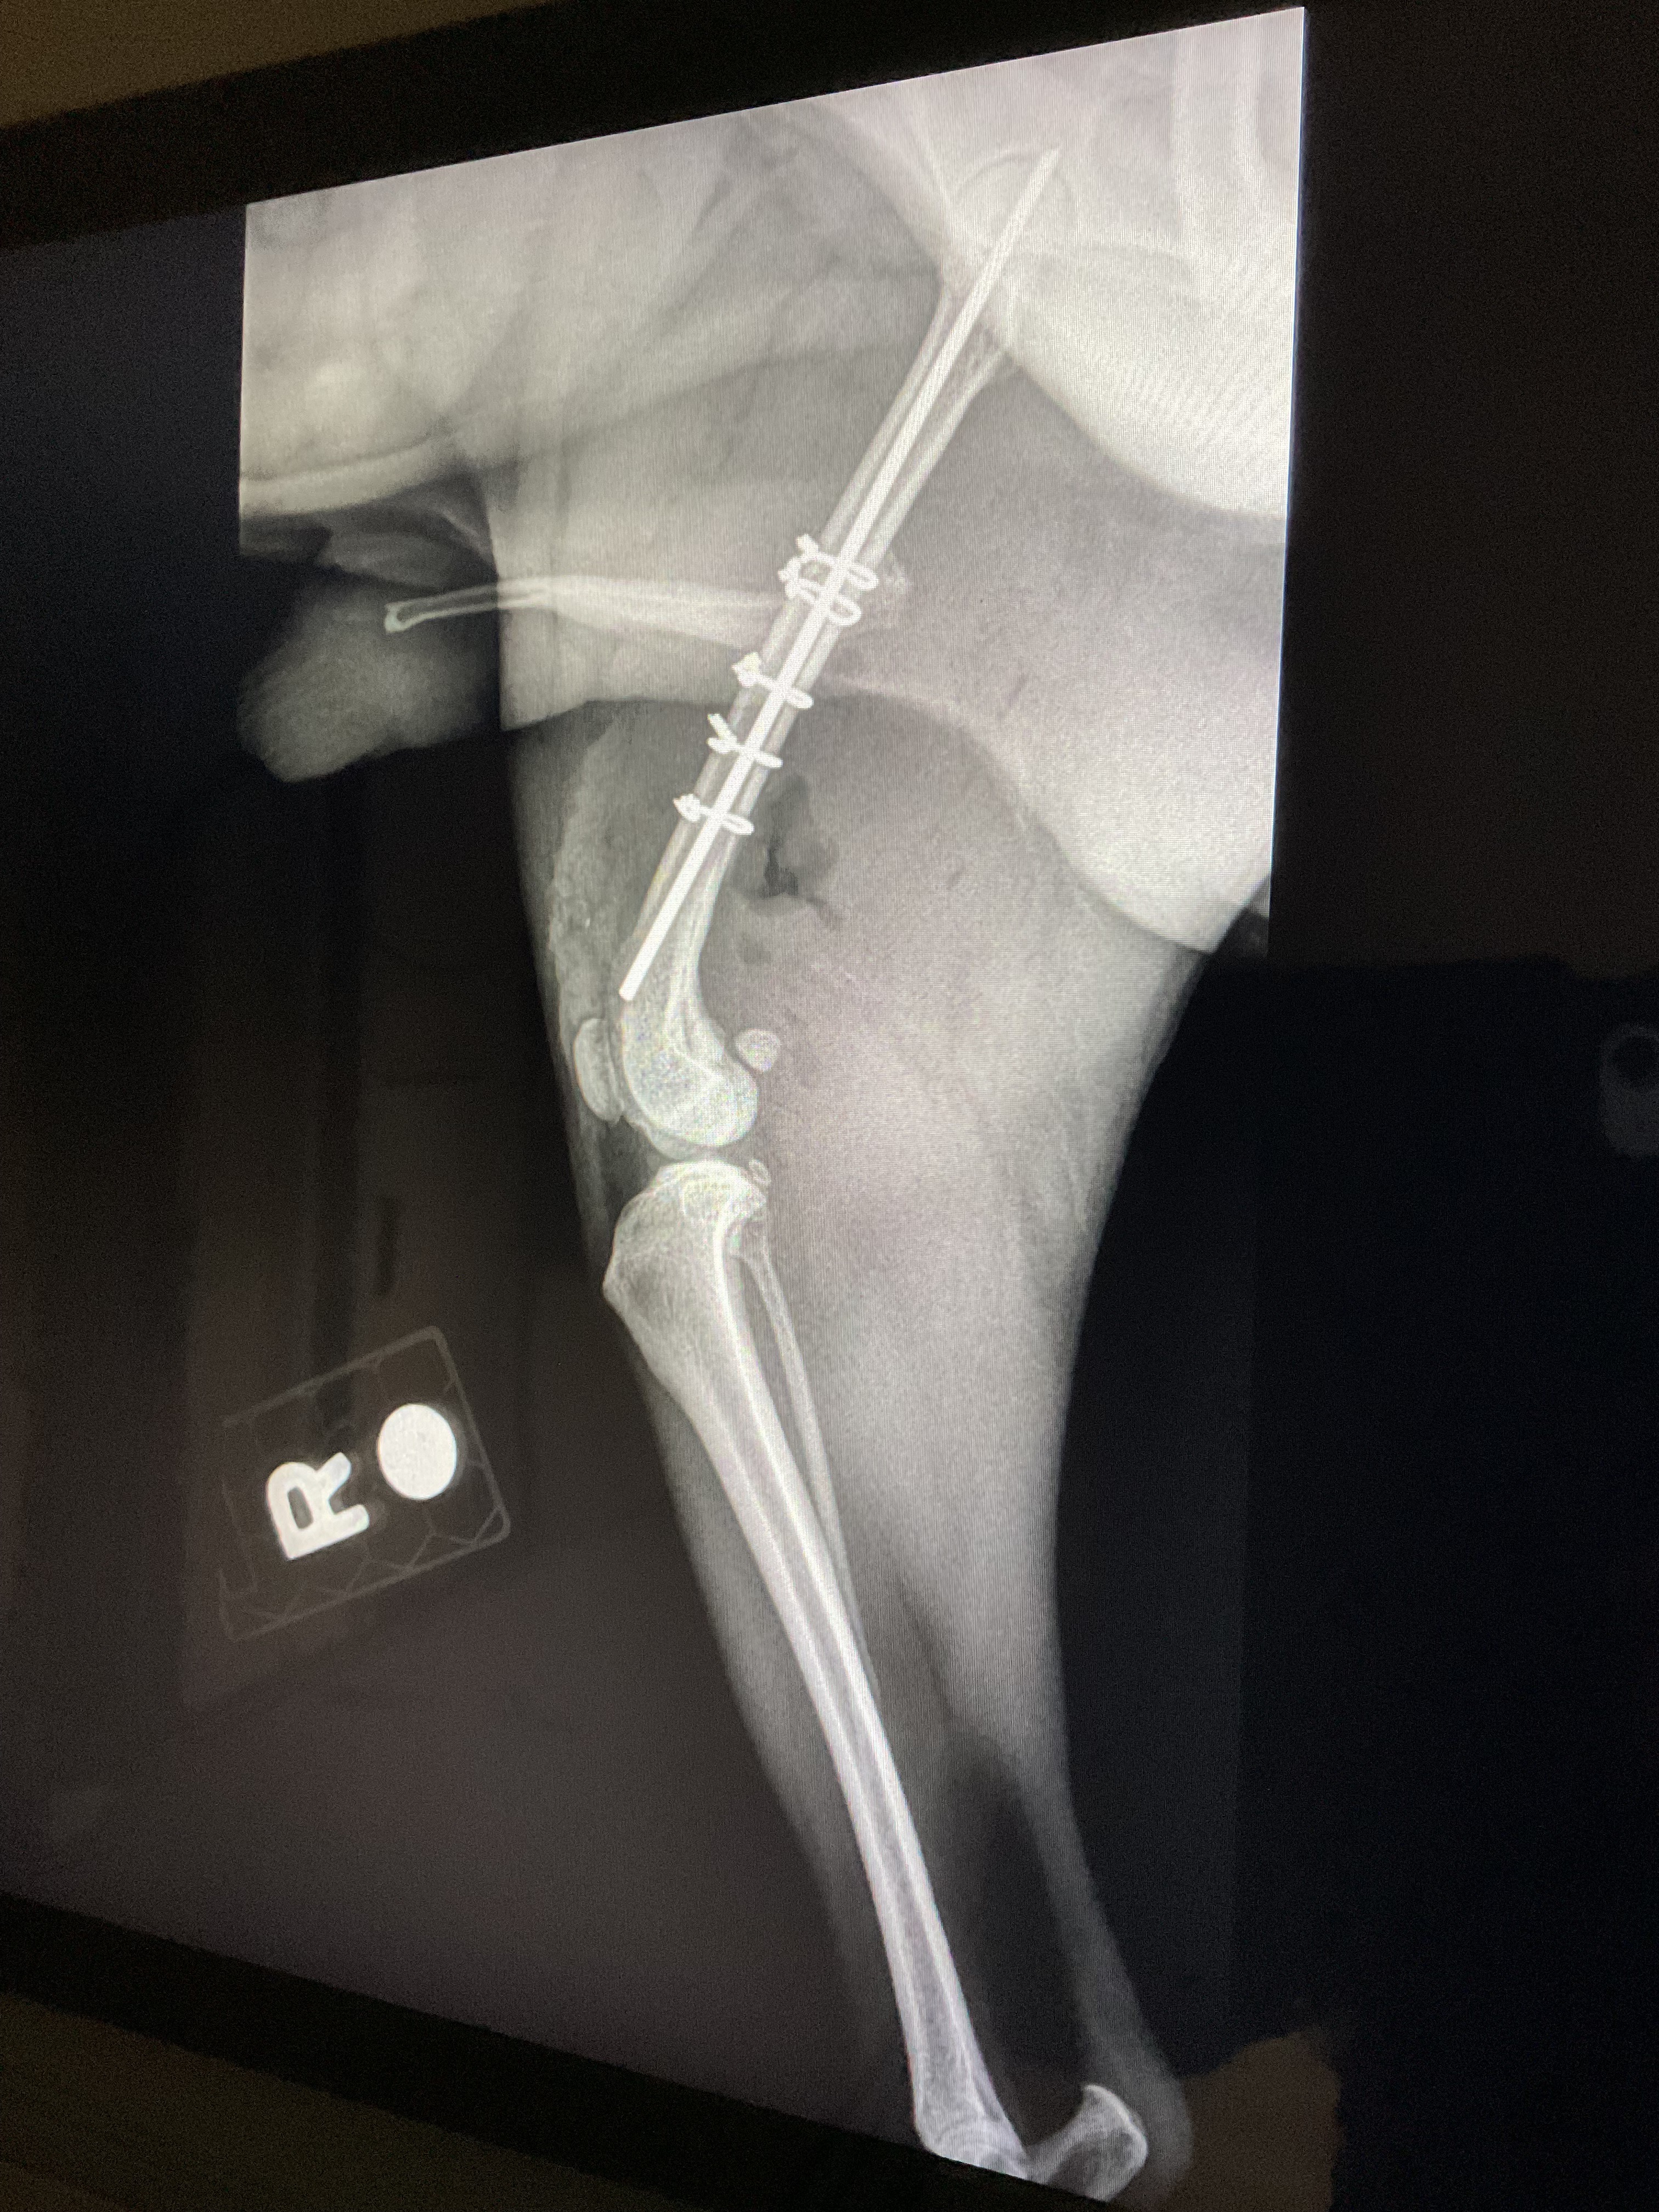

Second update: Roscoe has been admitted for surgery set for tonight. Please pray for his speedy recovery!!!

Update: 3:25a.m. Roscoe has a broken femur. His thigh is swollen and he’s given pain meds for now. Will need to take him to specialty hospital for a board certified surgeon evaluation in just a few hours. I’m told cost for surgery is between $8000 to $10,000, not including other miscellaneous fees. Either that I’m told to amputate his leg to save money. Seriously?!!! I’m all out of tears. I refuse to have his leg amputated because I don’t have the funds.